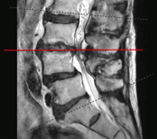

病患A右圖脊椎MRI橫切面腰椎3-4節顯示椎管內明顯狹窄。

診斷以病史與神經學檢查 為主。當臨床懷疑神經受壓、症狀持續或需規劃介入/手術治療時,醫師常會安排 MRI(磁振造影) 或必要時的 CT,以確定壓迫的節段、程度與合併病變(例如椎間盤突出或滑脫)。